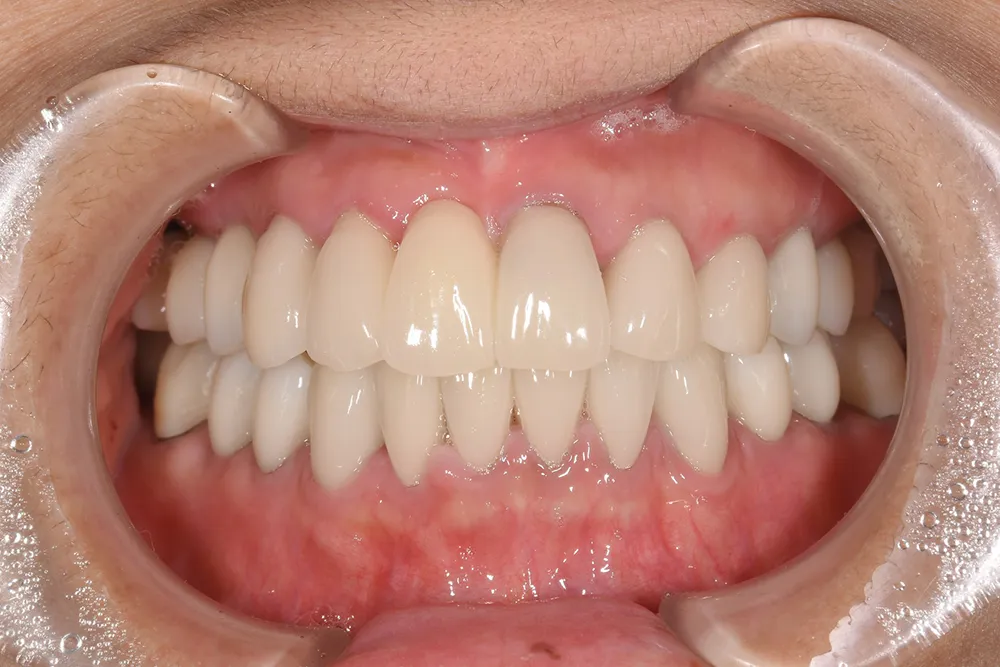

主訴 かみ合わせの機能障害と見た目の審美性を高めたい

治療方法 全顎をオールセラミック補綴で治療

治療期間 約1.5年

通院回数等 30回

費用 4,004,000円(税込)

リスク・副作用 治療期間が長くなる